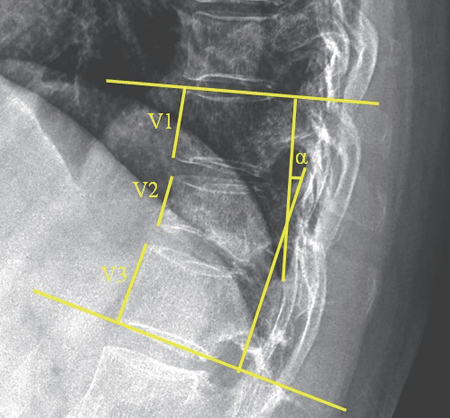

연구팀에 따르면 42명의 환자는 로모소주맙(제품명 이베니티)을 1년간 매월 1회 주사했고 44명의 환자는 척추 성형술을 받은 후, 각각 데노수맙(제품명 프롤리아) 주사를 투여받았다. 이후 연구팀은 치료 이후 1년 후 각 그룹의 △통증 △골밀도 △척추 압박 비율 △콥 각도에 대한 수치 평가 척도(NRS) 등을 비교했다. 그 결과, 로모소주맙 주사 치료 그룹은 척추 성형술 치료 그룹에 비해 NRS 점수가 더욱 큰 폭으로 감소했고 요추 골밀도는 더욱 증가한 것으로 나타났다.